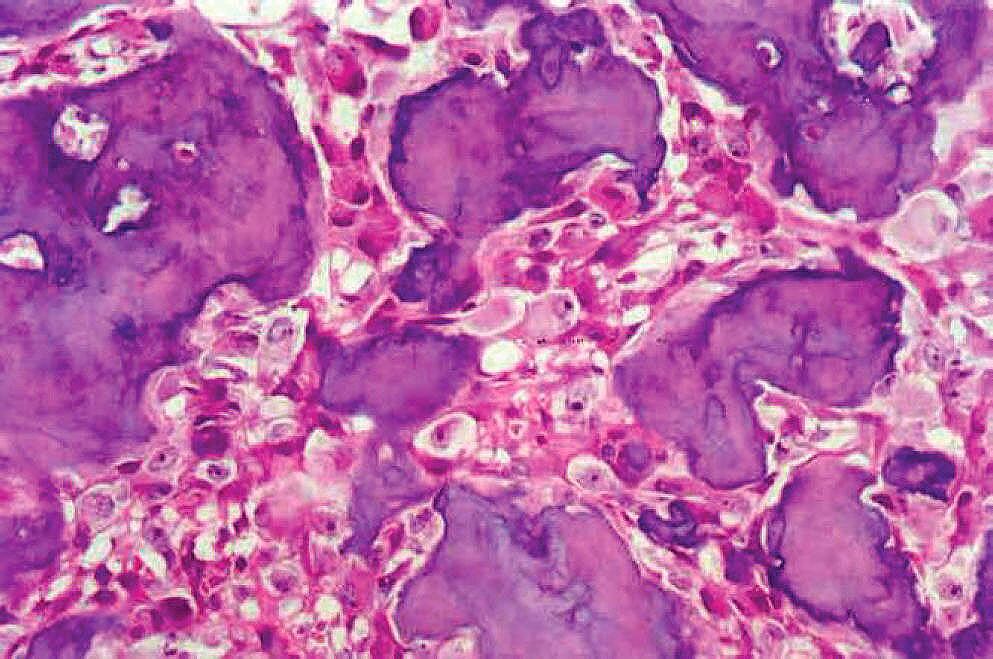

Qué es el osteoblastoma, un tumor que saltó a la fama recientemente

La enfermedad que, según revelaciones de un periodista, padece el cantante español Julio Iglesias, de 81 años, produce una inflamación que puede ser muy dolorosa. Aunque no se expande en el cuerpo, produce debilidad ósea y en las articulaciones.